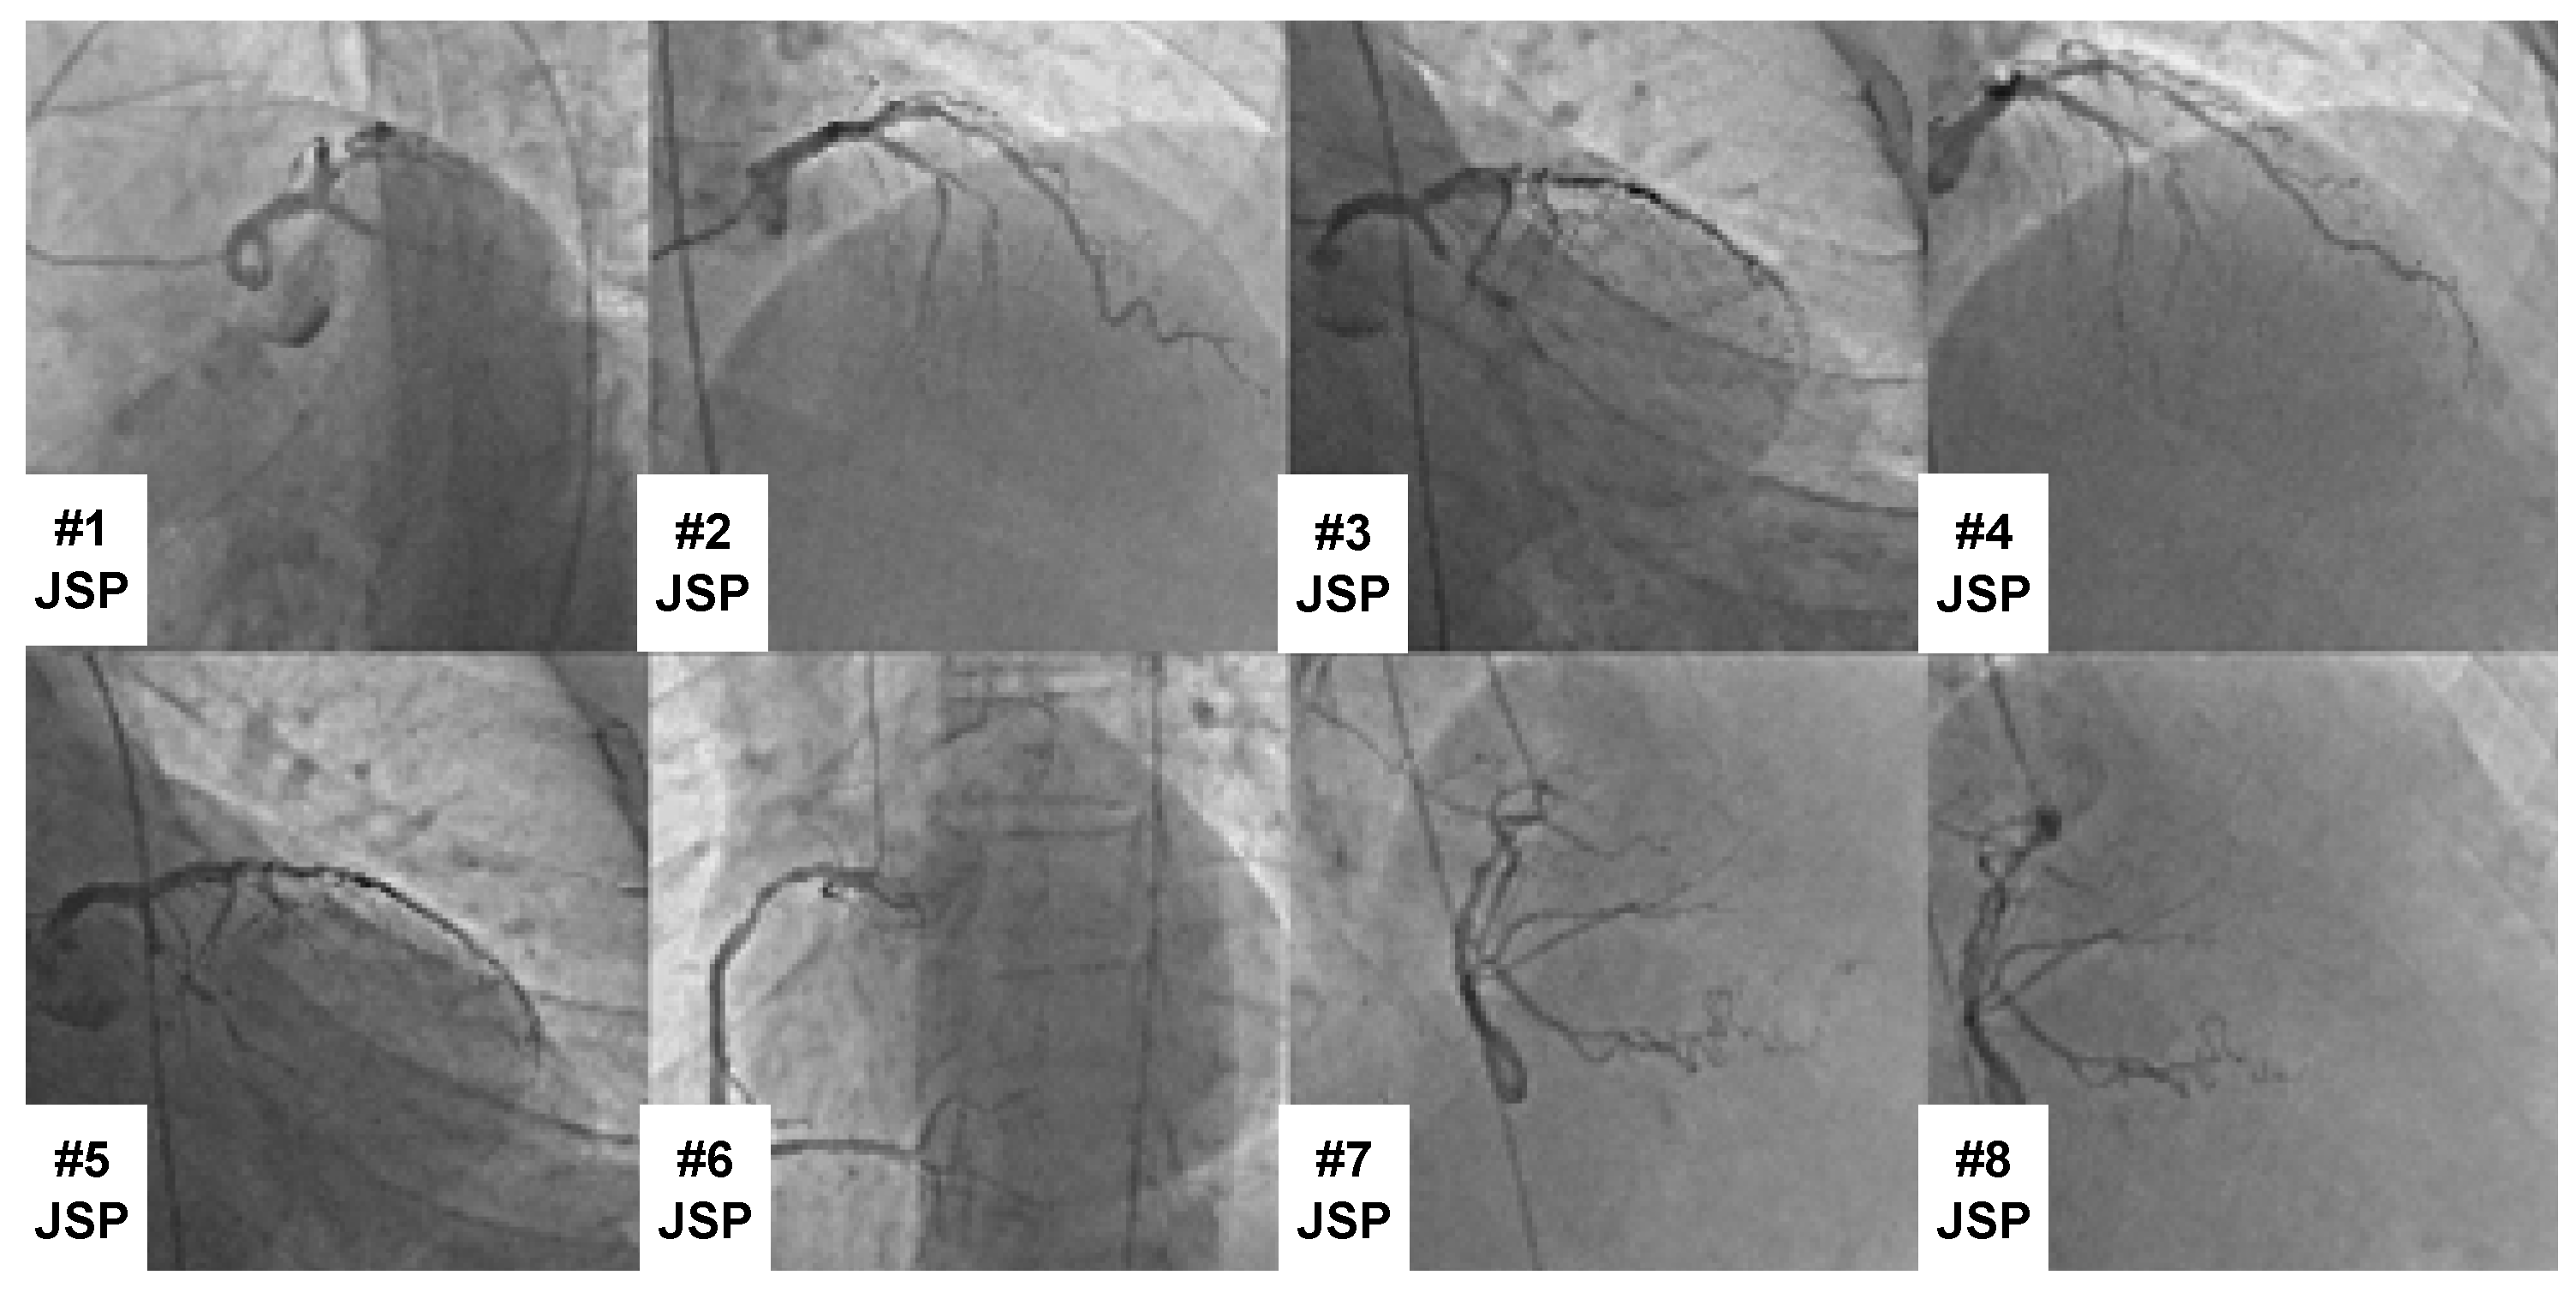

2. Datasets

Cardiologists at Fırat University gathered the dataset. Data were gathered using 12-channel digital ECG equipment. XML format was used to store the data, and 500 Hz and 1 KHz sample frequencies were used. The dataset’s primary coronary artery occlusions were designated as CX, RCA, and LAD. The designations CX + LAD, RCA + LAD, RCA + CX, and RCA + CX + LAD were used for several major coronary artery occlusions. Cardiologists used CAG for every ECG acquisition to ensure proper labeling. In addition, two different cardiologists performed the labeling separately to ensure labeling reliability. Different labeling errors were then resolved by agreement between the cardiologists. Following the CAG technique, a CAG image with the label CX + LAD obscured is displayed in Figure 1. This allowed for the recording and labeling of 1321 12-channel digital ECG signals. All of these ECG data were obtained from patients aged between 40 and 85 years. Of these patients, 592 were female and 729 were male.

ECG signals from the CX class (180), RCA class (185), LAD class (252), CX + LAD class (183), RCA + LAD class (173), RCA + CX class (156), and RCA + CX + LAD class (192) are all included in the dataset. Figure 2 displays a comprehensive 12-channel ECG signal representation for the major coronary artery that is occluded by CX. Figure 3 displays an example of a digital ECG signal sample from each class.

Figure 1. A CAG image with the label CX + LAD occluded following CAG processing.